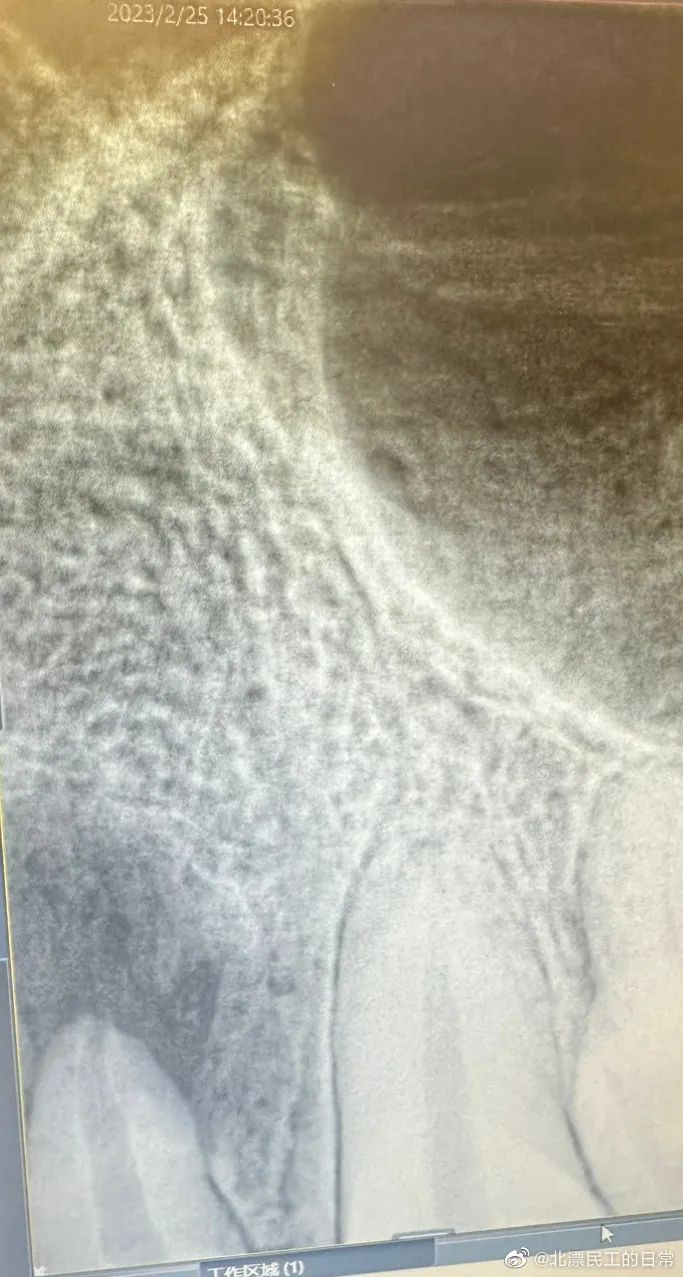

助手带我到一个小房间,类似电话间,然后用一个小仪器夹住我的牙齿,就完成了X光拍摄。

然后回到科室,医生指着片子说,你这个发炎很严重啊,需要根管治疗。